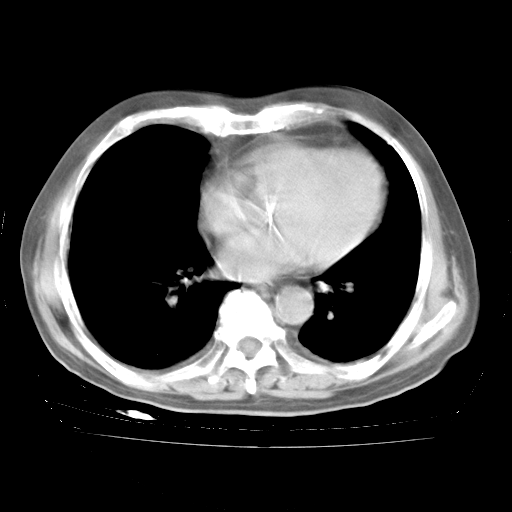

4月28日肺部CT